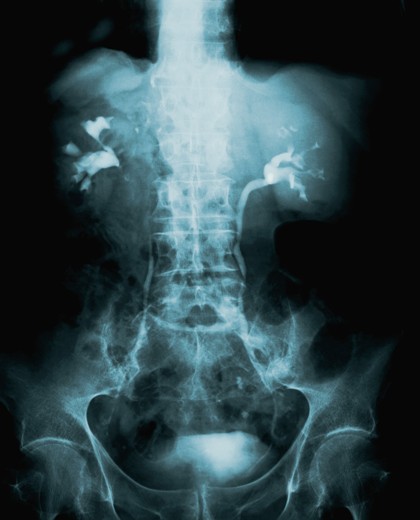

back-and-neck-pain.jpgNeck pain and back pain are two of the most common symptoms for which patients seek medical treatment. Pain occurs suddenly or develops gradually. The pain may be located in one area or throughout the lower back or through the legs and feet.

There are multiple causes leading to spinal pain, to name a few, damage to the bones, disks, muscles or joints of the spine, all resulting from injury or degenerative disease. These various causes all require medical attention.

Patients will undergo a comprehensive medical history and physical examination. If any tests are necessary for diagnosis, they will be ordered by our staff. Depending on the symptoms displayed, testing may include x-rays, CT scans, MRI scans, nuclear scans, electromyograms (EMGs) and/or blood work.  All tests will be performed at New York Methodist Hospital and results will immediately available for the physician to review.